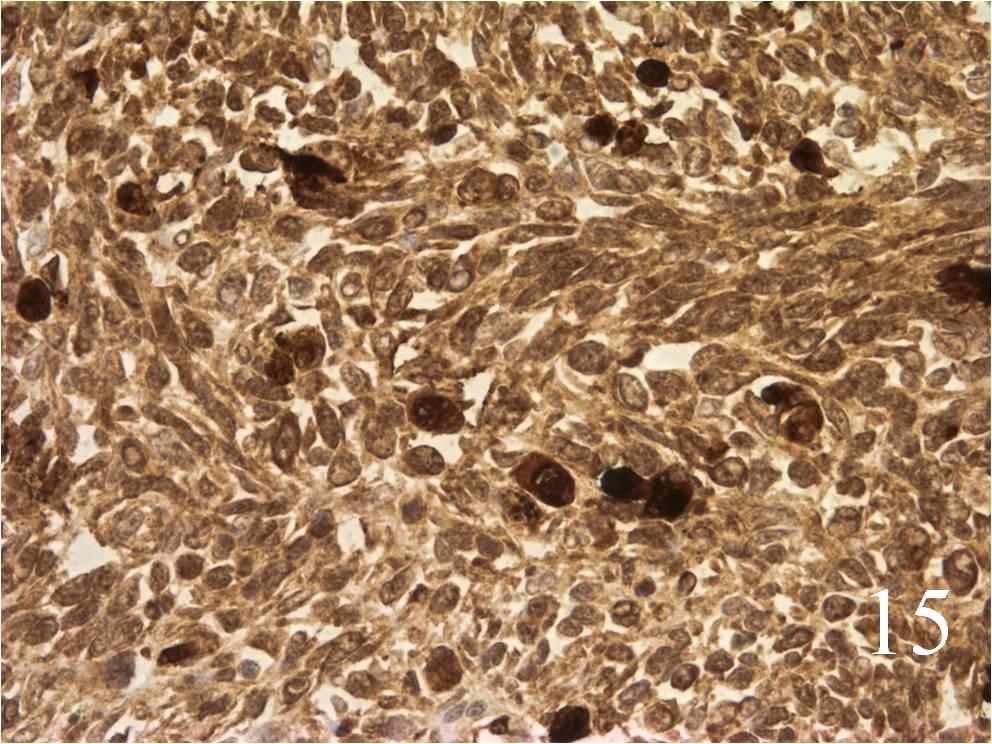

Microscopic

- Small round blue cells (Fig. 12-15)

Immunohistochemistry

- Vimentin positive; Keratin negative

- Actin variable; perhaps minor scant staining

- S-100 negative